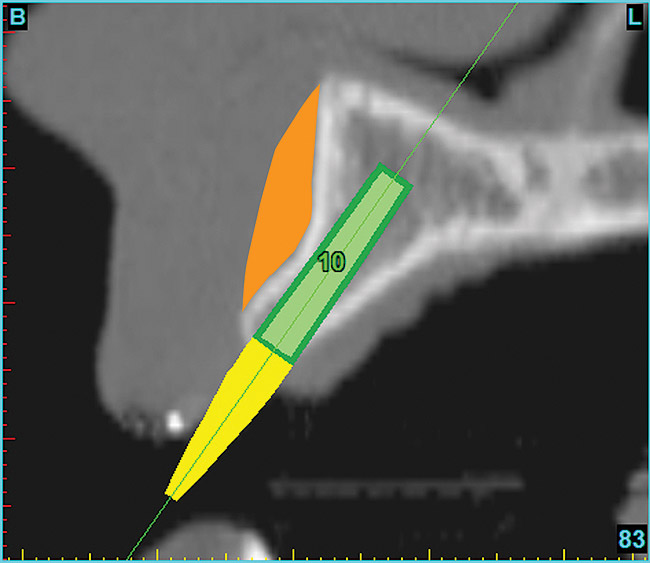

Using the interactive treatment-planning software application, the scan data was assimilated and both potential lateral incisor implant receptor sites were evaluated. It is a combination of the data and the methodology used to interpret the data that is the basis for defining a new paradigm in diagnosis and treatment planning. Proper evaluation of these images and correct use of the interactive treatment planning software tools is essential in creating a decision tree of treatment options. First, the data from the scan was reformatted into panoramic, axial, and cross-sectional images. The undistorted cross-sectional images revealed the residual alveolar bone in the area of the right lateral incisor. Then, a simulated schematic implant was placed within the bone with an abutment extension to help visualize the connection to the restorative position of the tooth (Figure 6). The Triangle of Bone® (TOB), a concept developed by the author to analyze bone quality, quantity, and disposition at prospective dental implant sites using CBCT scans, aided in determining available bone volume by defining a “zone” for proper implant placement18,19 (Figure 7).

After reviewing the CT data and the decision tree, the bone within the “zone” of the TOB was evaluated and found to be satisfactory for implant placement. Because the goal of implant dentistry is not the implant but the tooth that is placed, true restorative-driven implant dentistry must begin with the assumption that the implant position should remain consistent with the tooth it is replacing, and the final implant-supported restoration.12,22-26 The TOB aids the clinician in understanding the link between the implant position and the desired restorative goal. The base of the geometric shaped “zone” is visualized by starting at the widest area of alveolar bone facially and superiorly. The apex of the triangle is positioned to bisect the alveolar crest (Figure 7). The TOB, the overlay in the cross-sectional image, reveals whether adequate bone is available for implant placement. It also helps to identify concave facial bone defects, and accurately determine the width of bone at the crest. The author recommends using an interactive software application that provides the necessary measurement tools to accurately assess the bone anatomy.

Figure 7  SOFTWARE IMAGING The determination of the

Figure 7